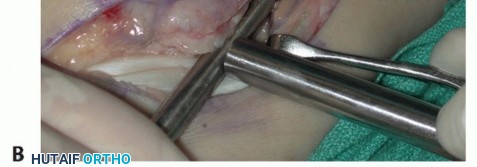

TECH FIG 1 • A. Intraoperative photograph of a left ankle (lateral approach) shows the peroneal tendons subluxing anteriorly (brevis is the gray arrowhead , longus is the white arrowhead , SPR is the black arrow). B. The peroneal tendons have been retracted anteriorly by the Penrose drain. Elevation of an anterior-based periosteal flap (outlined by dots) from the fibular groove has been completed. The black arrow shows the remnant of the SPR posteriorly. C. The tendons are relocated, after a groove-deepening procedure, into the recreated groove. The white dots outline the anteriorly based periosteal flap. It is then brought over to the posterior remnant of the SPR (black arrow). D. The flap is sutured to the remnant SPR with nonabsorbable sutures, completing the superior peroneal retinaculoplasty. |

| Make an incision in the peroneal sheath along the posterior border of the fibula. Retract the peroneal tendons anteriorly (TECH FIG 1B). | |||

| We routinely reinforce the SPR with a soft tissue periosteal flap elevated from the fibular groove from a posterior to anterior direction. | |||

| Raise the periosteal flap, measuring about 1.0 × 3.0 cm, sharply, from posterior to anterior. After the flap is | |||

| raised, a groove-deepening procedure may be performed when indicated. | |||

| Reduce the peroneal tendons and use the periosteal flap to contain the tendons, with the visceral side of the periosteum facing the tendons (TECH FIG 1C). | |||